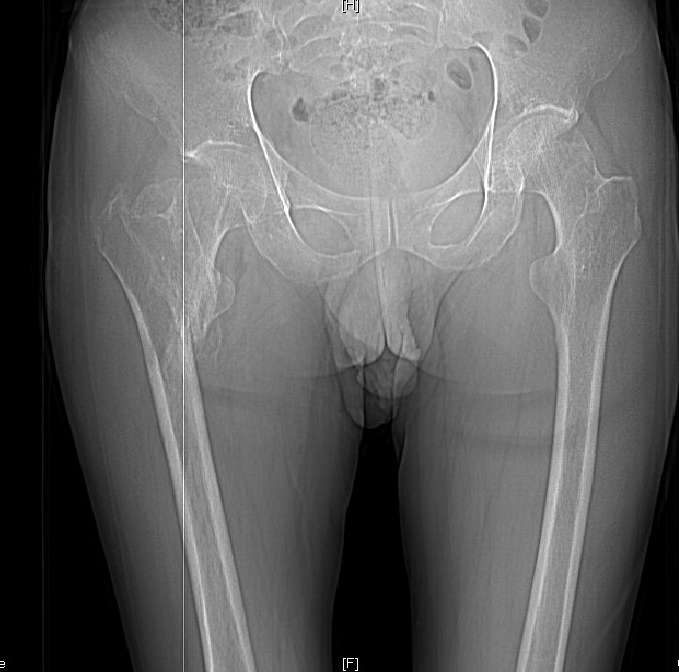

Доброго времени суток, уважаемые коллеги! Больному 45 лет. Лечили в

сельской больнице на скелетном вытяжении 6 нед. по поводу

межвертельного перелома бедренной кости с последующим наложением

кокситной повязки еще на 2 мес.

С момента травмы прошло 5 месяцев, ходит с костылями без нагрузки,

контрактуры в коленном и в тазобедренном суставах. Снимки во

вложении. У нас мнения разделились. Показанием для открытого

остеосинтеза мы считаем неустраненное ротационное смешение

дистального фрагмента, которое может привести к нарушению биомеханики

в тазобедренном суставе с последющими вытекающими последствиями. ЭОП

на сегодняшний день недоступен нам, а остеосинтез угловыми

пластинами, что можно попытаться, имеет определенный риск. Как быть?

Начать разработку в суставах и активизировать больного, что не было

сделано до этого, или всё-таки оперировать? Будем рады Вашим советам.